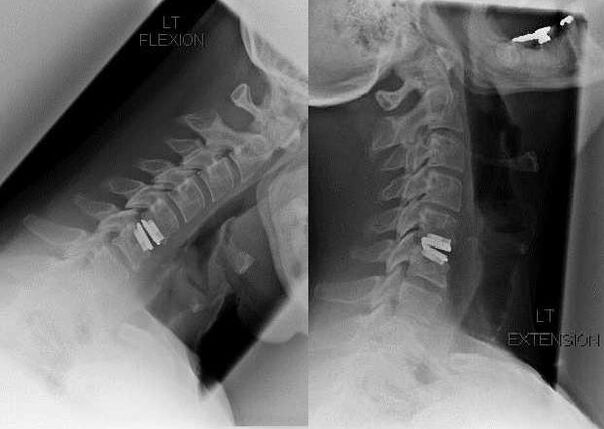

Chirurgická intervence

Indikace k chirurgické intervenci zahrnují neúčinnost konzervativní léčby, stejně jako komplikace cervikální osteochondrózy, například diskogenní myelopatie, syndrom vertebrální arterie a radikulární syndrom. K dekompresi míchy, krevních cév a míšních kořenů se provádějí následující operace:

- laminektomie;

- laminotomie;

- foraminotomie;

- facetektomie;

- discektomie.

Během operace mohou být vyříznuty kostní fragmenty a vazy a mohou být zcela nebo částečně odstraněny meziobratlové ploténky. U malých herniálních výběžků se často provádí laserová vaporizace jádra disku.

Po excizi obratlových struktur je často vyžadována stabilizace pohybových segmentů páteře spinální fúzí nebo instalací kostních a dermálních autograftů.